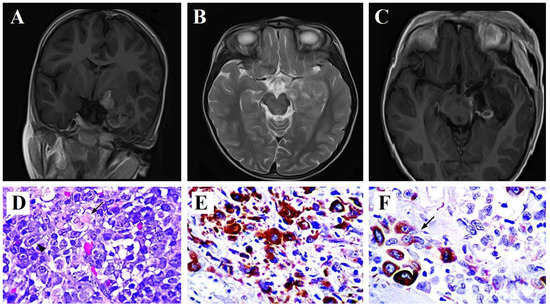

2. Case Report